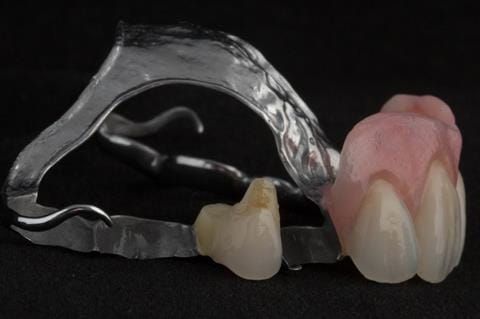

- UR2 peri-radicular periodontitis with a peri-radicular area on the root apex. Retrograde amalgam filling from a previous apicectomy. No visible root canal or root canal filling. Large circumferential marginal gap between the crown and tooth. Large post and core present. Very little tooth structure remaining resulting in a fragile tooth with increased potential for fracture.

- UR1 peri-radicular periodontitis with a small peri-radicular area on the root apex with wide blunderbuss apex. Radio-opaque root canal filling present approximately 3 mm short of the radiographic apex. Large circumferential marginal gap between the crown and tooth. Large post and core present. Very little tooth structure remaining resulting in a fragile tooth with increased potential for fracture.

- UL1 peri-radicular periodontitis with a peri-radicular area on the root apex. Retrograde amalgam filling from a previous apicectomy. Visible root canal space with no sign of root canal filling. Large circumferential marginal gap between the crown and tooth. Large post and core present. Very little tooth structure remaining resulting in a fragile tooth with increased potential for fracture.

- UL2 peri-radicular periodontitis with a peri-radicular area on the root apex. No visible root canal or root canal filling. Large circumferential marginal gap between the crown and tooth. Large post and core present. Very little tooth structure remaining resulting in a fragile tooth with increased potential for fracture.

- High smile line showing gum above gingival zeniths of upper front teeth when smiling. Aesthetic failure of the upper four incisors with inflammation of the gingivae and mis-match of the gingival zenith levels.

- Other than the maxillary incisors the remaining dentition was in marginally better condition being moderately to heavily restored. Many will probably require replacement and restoration from time to time mainly from wear and tear owing to occlusal forces.